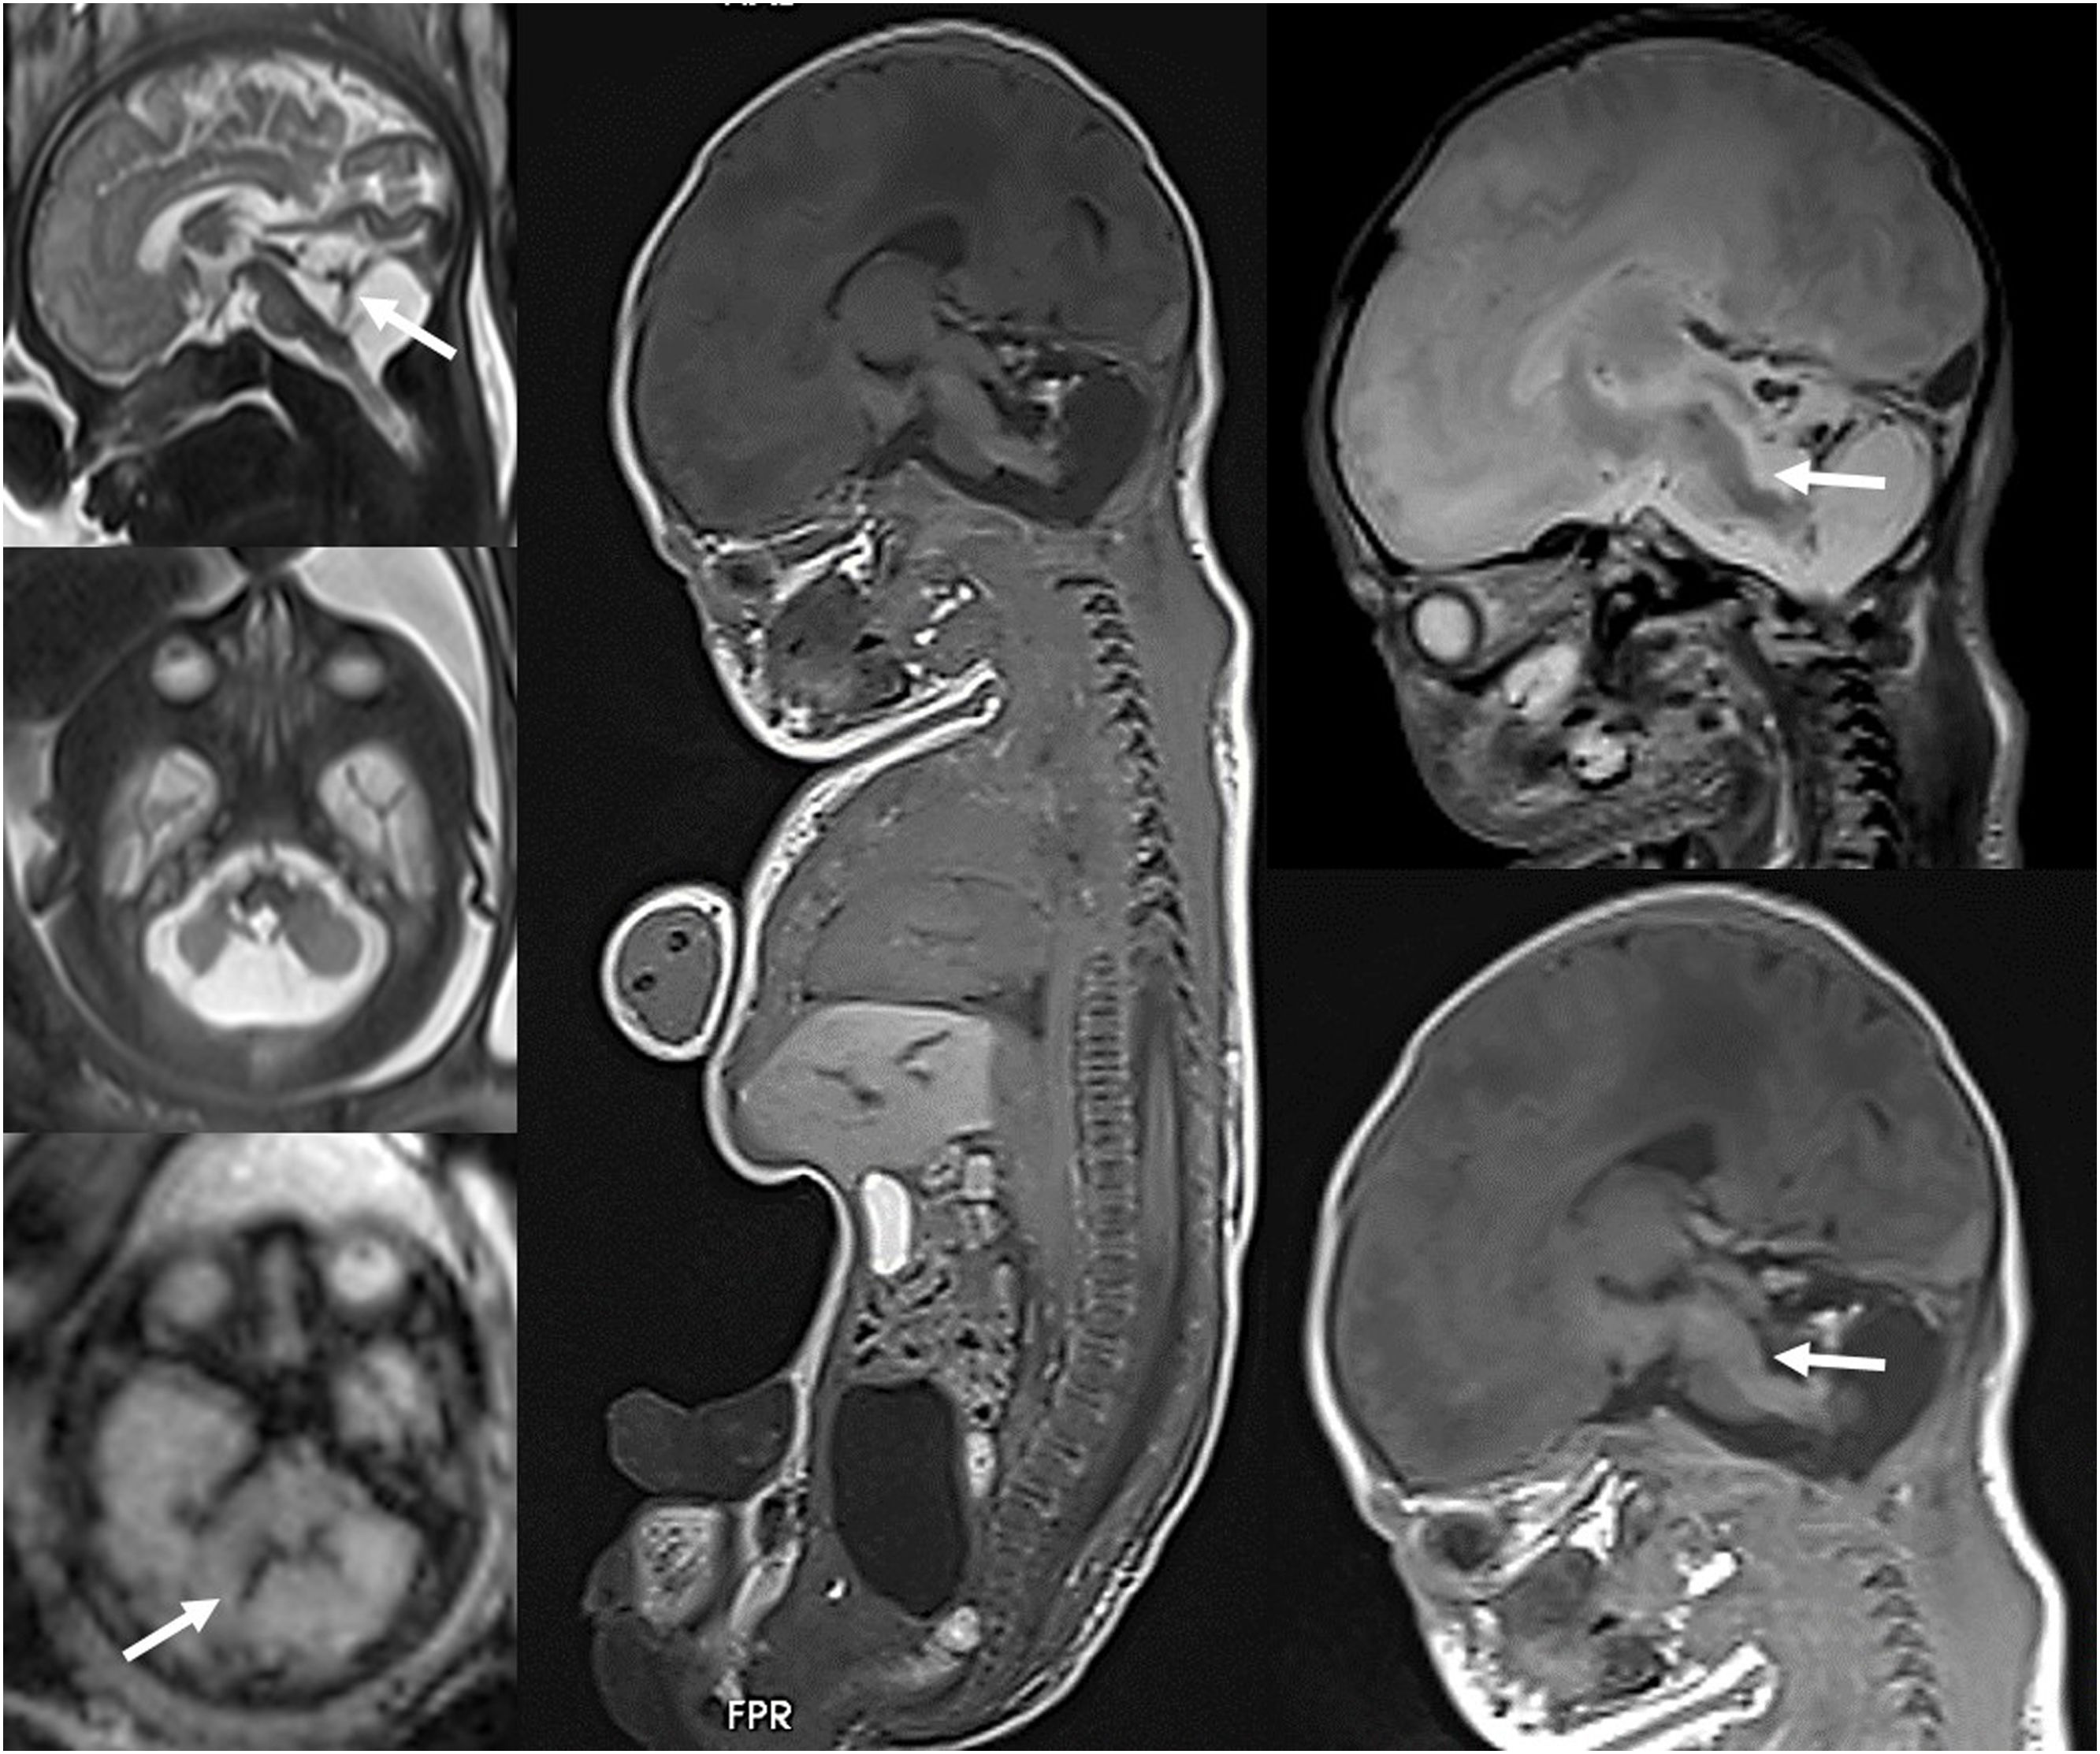

Feto de 33 semanas de gestación con hallazgo ecográfico de hipoplasia cerebelosa. A)RM fetal realizada a las 33 semanas, que demuestra una lesión clástica o destructiva del cerebelo con restos hemorrágicos (flechas). B)RM fetal post mortem tras la interrupción de la gestación que muestra la hemorragia cerebelosa, con hallazgo asociado de lesión tegmental del bulbo raquídeo (flechas), no evidenciada previamente.